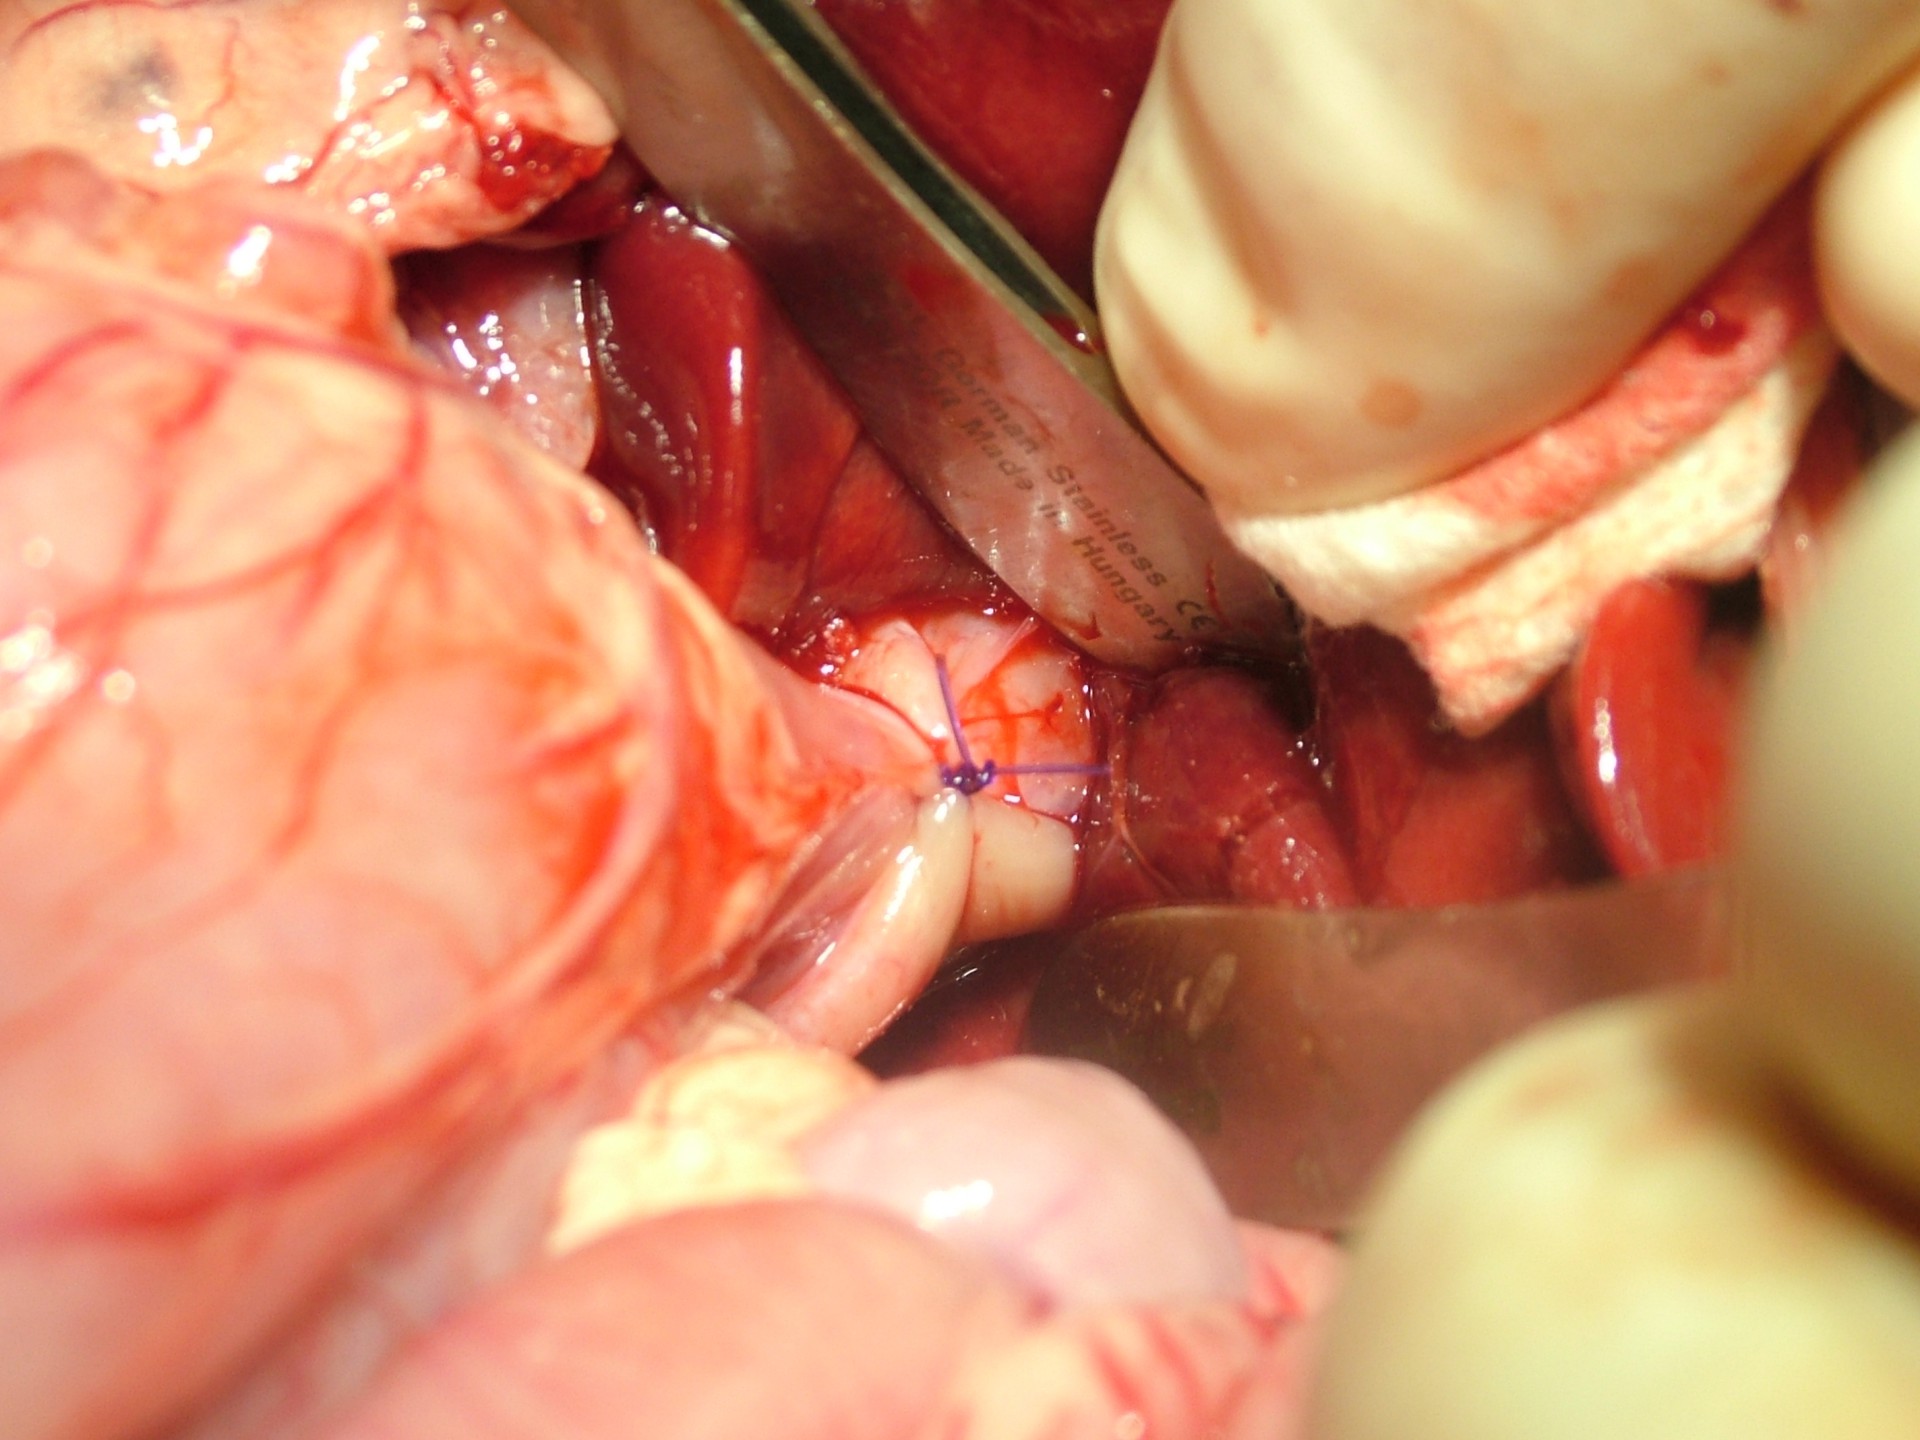

Mindhárom rekeszsérv forma meglehetősen ritkán fordul elő. A diagnózis felállítása a kórelőzmény, a klinikai tünetek a mellkas röntgenvizsgálata, a hasüreg ultrahangos vizsgálata alapján lehetséges.A rekeszsérv műtéti ellátása során a legnagyobb kihívást az jelenti, hogy a hasüreg megnyitását követően a sérvkapun keresztül levegő kerül a mellüregbe, ezáltal az állat spontán légzése leáll, így a műtét teljes ideje alatt asszisztált lélegeztetésre van szüksége.A műtét során a mellkasba előesett szerveket reponáljuk, a rekesz folytonosság hiányát megszüntetjük és a mellkasban lévő szabad levegőt eltávolítjuk, ezzel biztosítva az állat spontán légzését. A műtétet követő napokban legfontosabb feladat a vérkeringés és a légzés folyamatos, kórházi körülmények közötti kontrolálása.Az idejében felismert és megfelelően ellátott veleszületett rekeszsérv jó eséllyel gyógyítható, a traumás eredetű sérv ellátásának eredményességét általában az egyéb szervek sérülése határozza meg.